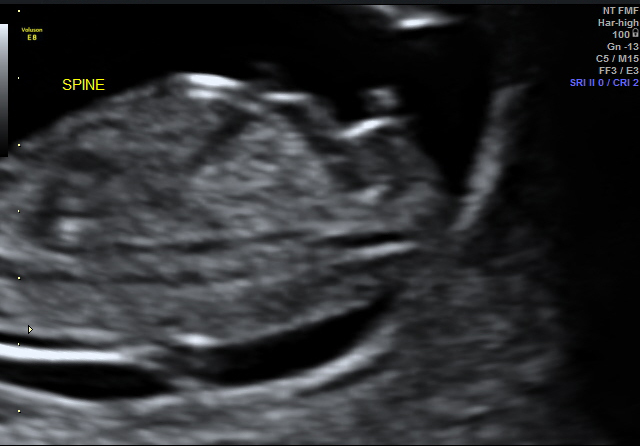

I don't have a complete shot head to toe of baby with nub exposed but I do have a close up... All guesses appreciated!